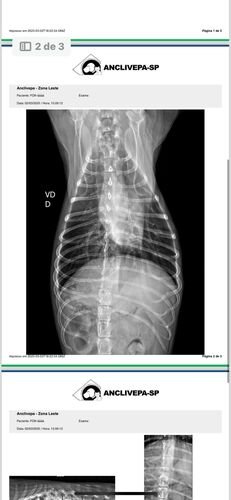

No dia 02 de março de 2025, Fox sofreu um grave acidente. Uma linha de pipa com cerol passou pela laje de casa e cortou a Fox. Assustada, ela caiu da laje de uma altura de 3 metros, sofrendo diversas fraturas nas patinhas e costelas, lesões internas que prejudicaram sua mobilidade.